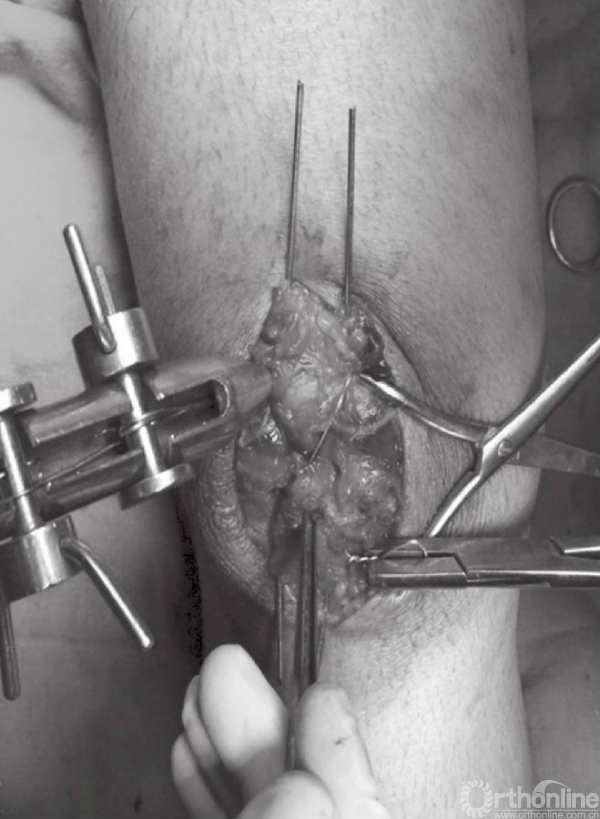

骨折端固定可采用1.6mm克氏针或者4.0mm空心螺钉。可在髌骨的中心部位,离髌骨前侧5~8mm处拧入2根克氏针或者2枚空心螺钉。也可采用克氏针以倒打的方式先穿过近端骨折块,在复位后再穿过远端骨折块(图7~10)。

图7 A~C以逆行打入的方式在骨折近端置入克氏针,离髌骨前侧约5mm

图8 置入的两枚的克氏针应保持平行,位置约为髌骨的大致1/3及2/3位置

图9 在复位钳的帮助下完成髌骨骨折复位以及临时固定

图10 在临时固定的同时,将克氏针穿过远端骨折块